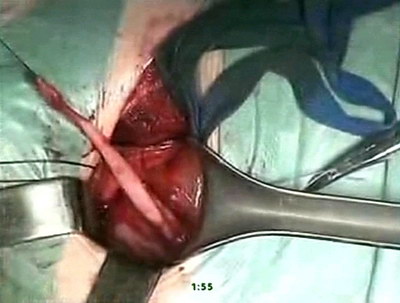

Под эндотрахеальным наркозом произведен разрез по Пфаненштилю,

послойно с поперечным рассечением апоневроза, тупо разведена

прямая мышца живота, выделена и взята на держалки передняя

стенка мочевого пузыря, последняя рассечена поперечно на

протяжении 5-6 см. Устья мочеточников визуализированы в

типичных местах. Поочередно с двух сторон выполнено выделение

устьев мочеточников, мобилизация нижних третей мочеточников

на протяжении 3-4 см. Мочеточники расширены до 15мм в диаметре,

в области интрамуральных отделов определяются их сужения.

Мочеточники перекрёстно уложены в подслизистый тоннель между

устьями в области треугольника Льето. Выполнена резекция

мочеточников на протяжении 2 см и анастомоз со слизистой

мочевого пузыря викрилом 4/0 выше устьев мочеточников. Слизистая

мочевого пузыря ушита викрилом 4/0. Мочеточники интубированы.